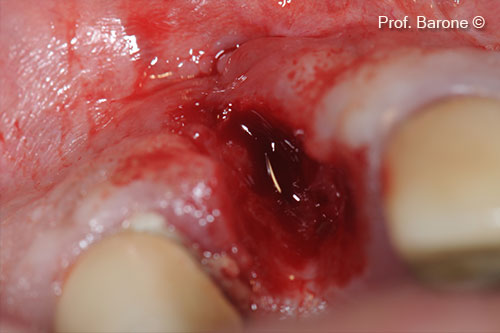

Hình ảnh nhìn từ phía má, răng số 11

Nhổ răng

Hốc răng mới nhổ được xử lý bằng miếng bọt biển Collagen và khâu chéo